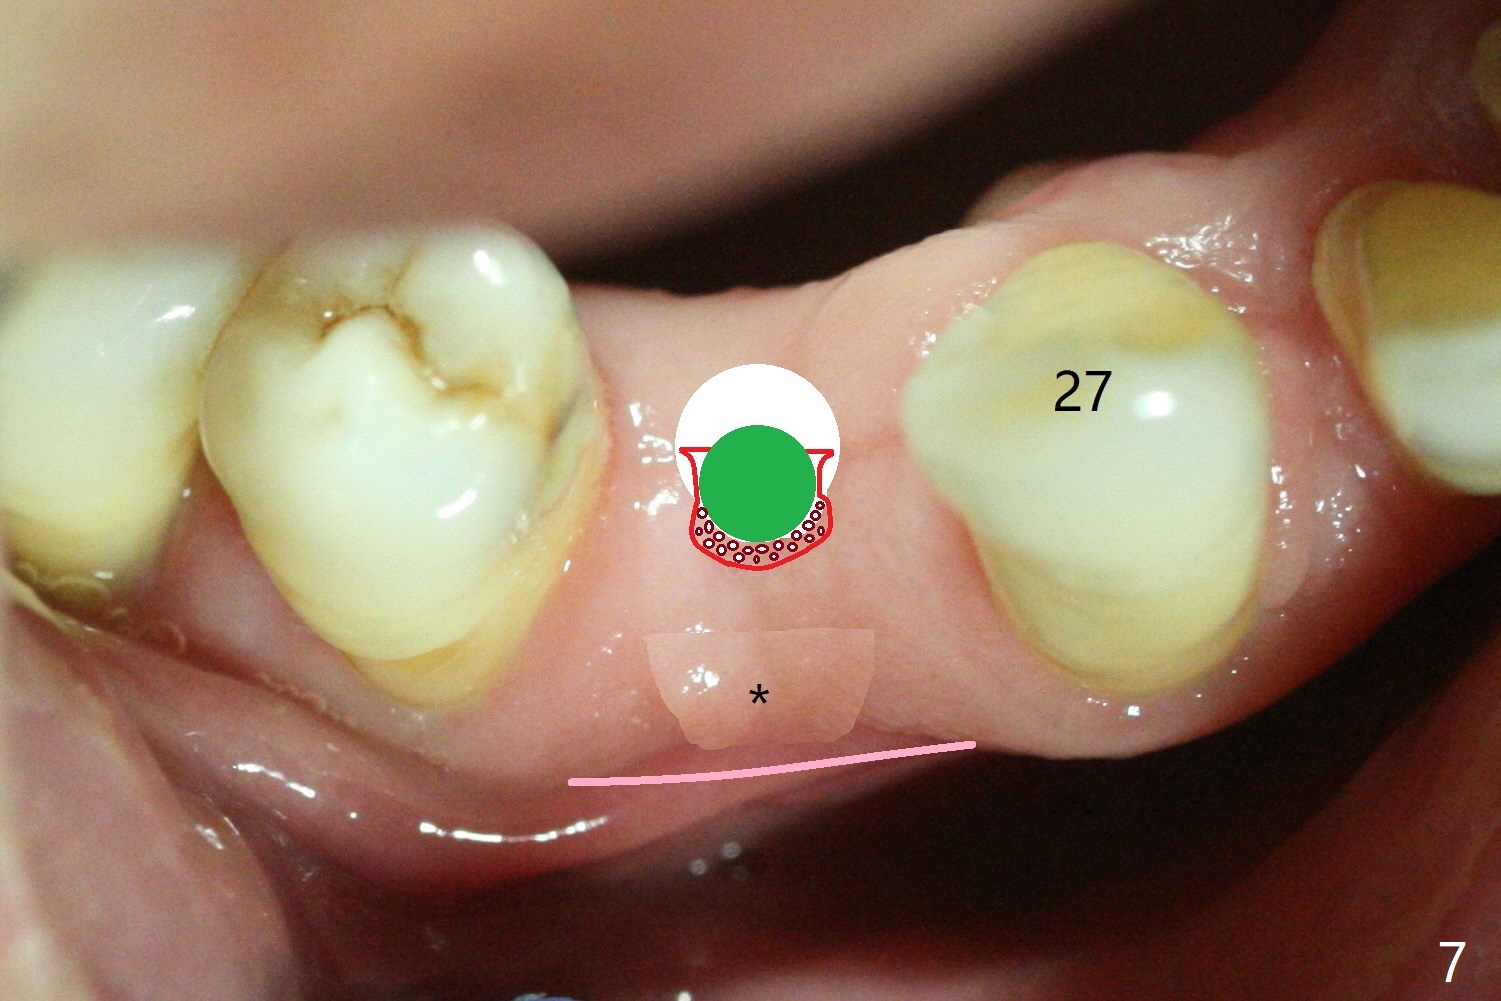

plate is further expanded buccally with a large expander (Fig.5). Bone graft

(Fig.6 red) is placed buccal.

Implant (Fig.7 green) placement further bone and soft tissue

expansion (pink line).